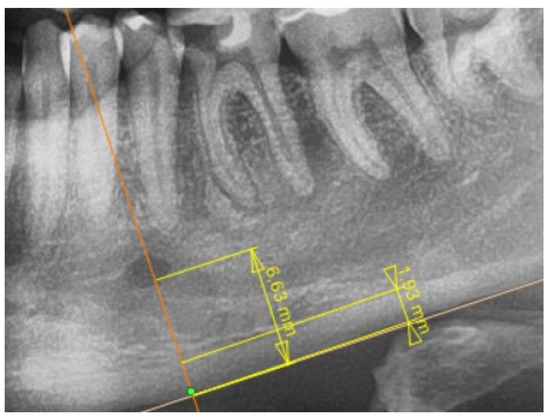

2.2. Radiological Study Protocol

- Benson, B.W.; Prihoda, T.J.; Glass, B.J. Variations in adult cortical bone mass as measured by a panoramic mandibular index. Oral Surg. Oral Med. Oral Pathol. 1991, 71, 349–356. [Google Scholar] [CrossRef]

- Khaitan, T.; Shukla, A.K.; Gupta, P.; Naik, S.R. Is panoramic mandibular index a reliable marker in the evaluation of bone mineral density and sexual dimorphism? J. Forensic Dent. Sci. 2019, 11, 133–136. [Google Scholar] [CrossRef] [PubMed]

- Maćkowiak, P.; Kaczmarek, E.; Kulczyk, T. Cortical width measurement based on panoramic radiographs using computer-aided system. In Bio-Informatic Systems, Processing and Applications; Abginya, J., Custovic, E., Whittingen, J., Eds.; River Publishers: Aalborg, Denmark, 2013; Volume 2.1, pp. 169–190. [Google Scholar]

- Karayianni, K.; Horner, K.; Mitsea, A.; Berkas, L.; Mastoris, M.; Jacobs, R.; Linfh, C.; van der Stelt, P.; Harrison, E.; Adams, J.E.; et al. Accuracy in osteoporosis diagnosis of a combination of mandibular cortical width measurement on dental panoramic radiographs and a clinical risk index (OSIRIS): The OSTEODENT project. Bone 2007, 40, 223–229. [Google Scholar] [CrossRef]